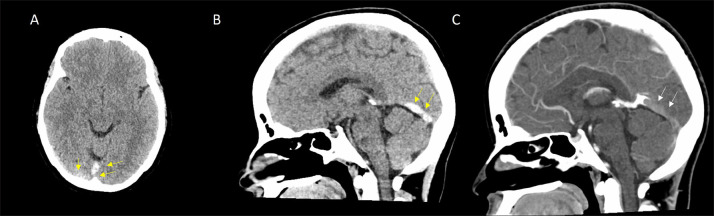

Abstract Image